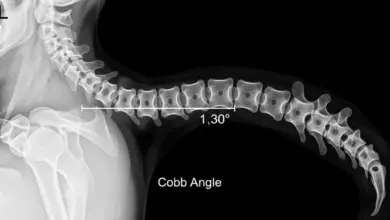

Como é a dor de cifose?

Se você está tentando entender como é a dor de cifose, a primeira informação importante é simples: muitas pessoas têm…